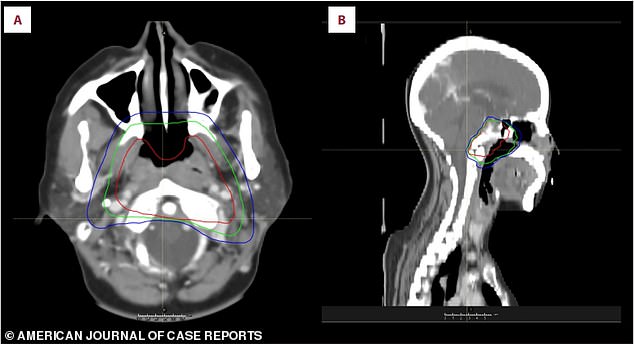

Physicians recommended an operation, but the woman refused because of worries regarding the dangers and impact on her lifestyle. She opted for several sessions of radiation and was completely healed from the illness afterward.

Physicians caring for the patient stated that imaging of both the brain and the nasopharyngeal region is essential for identifying this uncommon type of cancer.